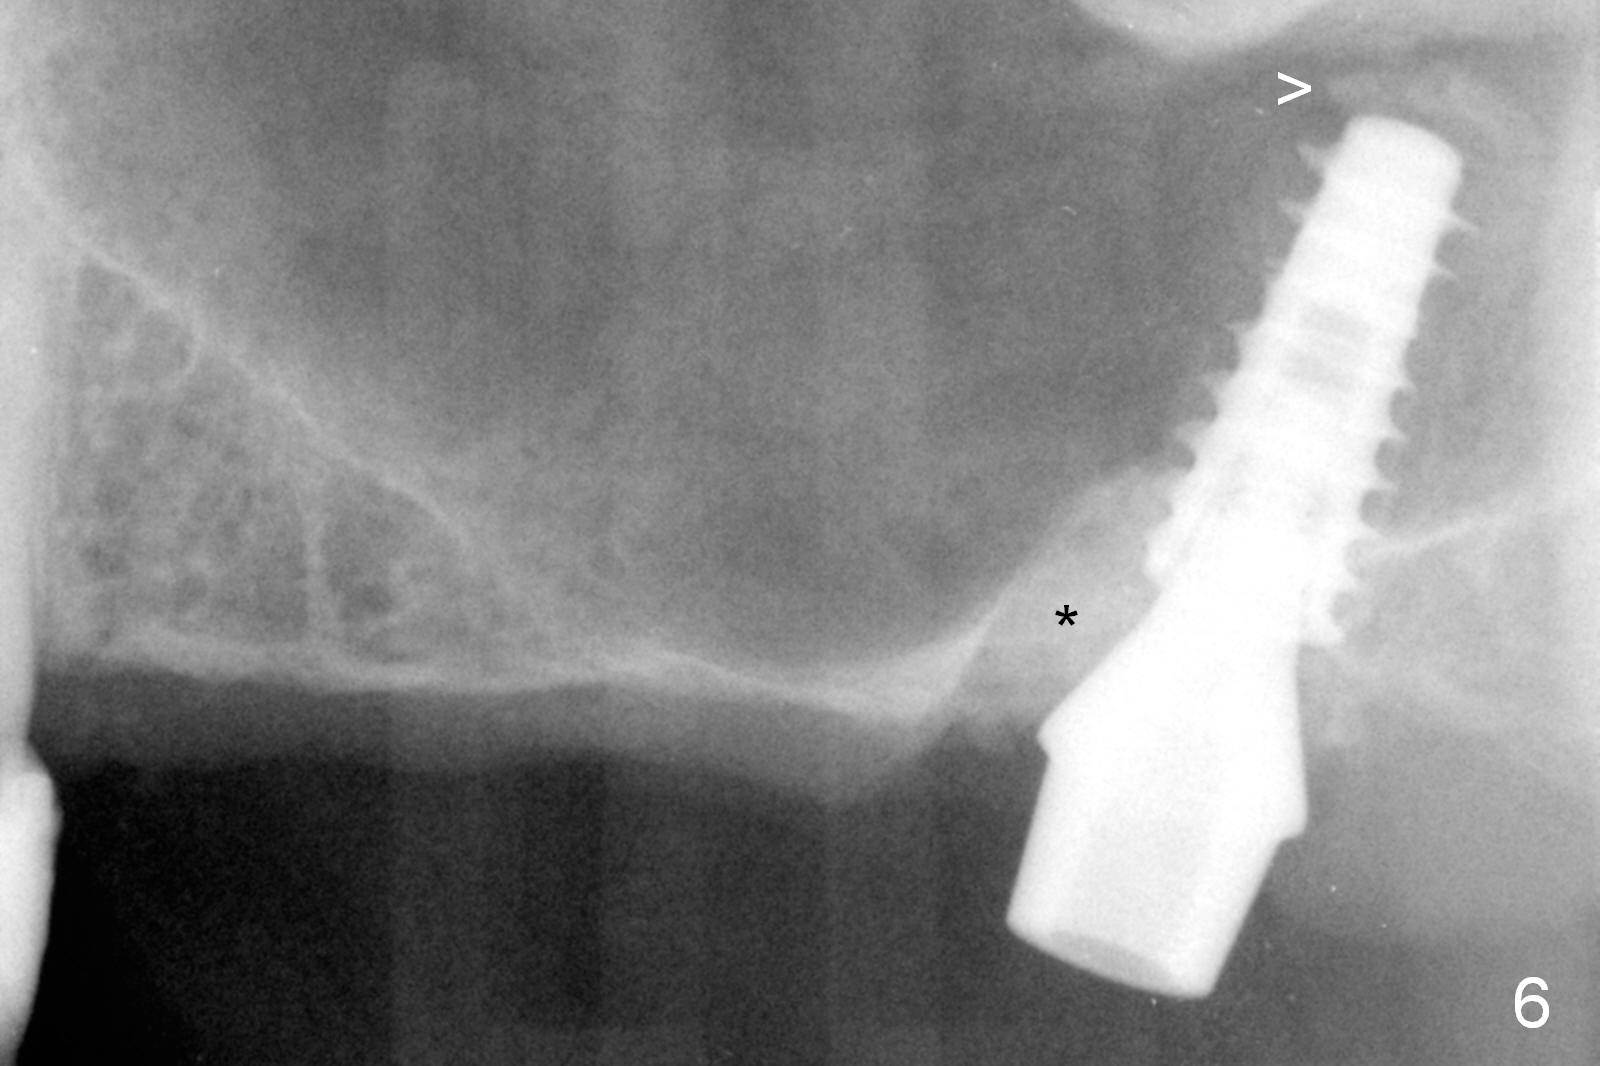

Fig.1,2 show the close relationship of the upper flipper and the residual roots at #15.  Atraumatic extraction using periotomes and surgical sectioning still results in perforation of the mesiobuccal socket (Fig.3 >).  The distobuccal one is shallow, while the septum is small.  It appears that the palatal (Fig.3 P) socket is the most ideal recipient site for the immediate implant and is expanded with Magic Osteotomes until 4.3 mm (Fig.4,5) with the coronal end pushed as buccal as possible.  After placing allograft for sinus lift (Fig.6 >), a 5x11 mm IBS implant is placed with insertion torque ~ 50 Ncm.  A 6x4(3) mm pair abutment is placed, followed by bone graft in the remaining sockets (Fig.6 *) and by Osteogen plug (Fig.7 *).  Finally the socket is sealed by applying acrylic over the abutment (Fig.8).  While the acrylic is setting, the flipper is seated and excess acrylic is removed and pushed away from the flipper (Fig.9).  Advise the patient not to wear the flipper.  If it is being worn, there will be minimal contact between the flipper and the immediate provisional.